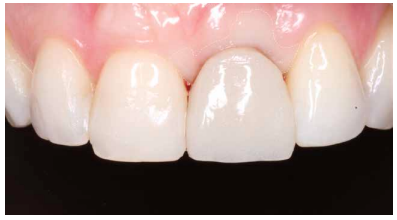

Conclusiones: La rehabilitación sobre implantes en situaciones de pérdida dental en el sector anterior estético y en especial, en pacientes jóvenes, requiere un plan de tratamiento multidisciplinar en cuanto a la extracción del diente y colocación del IOI en la posición tridimensional correcta, existiendo diferentes aspectos a tener en cuenta para ello, especialmente el remanente óseo residual, la posición del margen gingival, así como la preservación y acondicionamiento de los tejidos duros y blandos periimplantarios mediante injertos y un manejo correcto de una prótesis provisional hasta conseguir un perfil de emergencia y contorno gingival ideal antes de la corona definitiva

Conclusions: Rehabilitation on implants in situations of tooth loss in the aesthetic anterior sector, especially in young patients, requires a multidisciplinary treatment plan in relation to tooth extraction and placement of the OII in the correct three-dimensional position. There are various aspects to be taken into account, particularly the residual remaining bone, the position of the gingival margin, as well as the preservation and conditioning of the peri-implant hard and soft tissues by means of grafts and proper handling of a provisional prosthesis until an ideal emergence profile and gingival contour is achieved before the final crown.

Los beneficios de la carga inmediata incluyen una reducción notable de las intervenciones quirúrgicas, una menor dilatación temporal del tratamiento e incluso un mejor bienestar psicológico y social para el paciente. En casos con importante compromiso estético, la carga inmediata o la provisionalización inmediata, añadida a la colocación inmediata postextracción del IOI permiten minimizar las alteraciones derivadas de la pérdida dental, manteniendo el perfil de emergencia, contorno de tejidos blandos y las papilas gingivales5-7.

Así mismo, se han establecido diferentes protocolos para el manejo del sector estético anterosuperior, que se suman al acto de la colocación inmediata del implante y la corona provisional, donde se incluyen la colocación de un material no reabsorbible entre el IOI y la cortical vestibular para minimizar el posible colapso, así como el manejo de los tejidos blandos periimplantarios8-11.